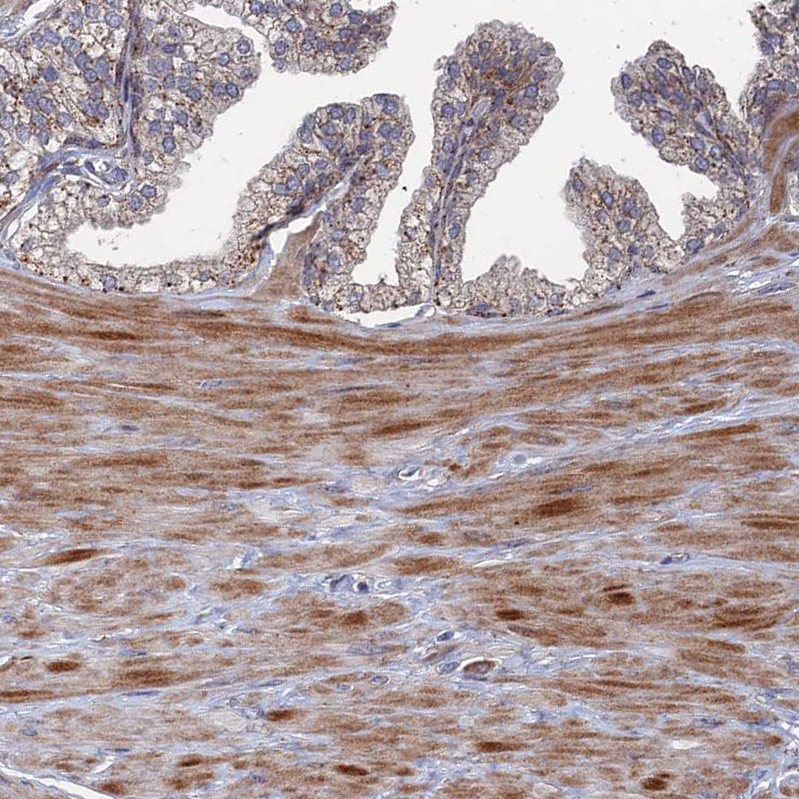

Immunohistochemical staining of human skin shows moderate to strong cytoplasmic and nuclear positivity in squamous epithelial cells.